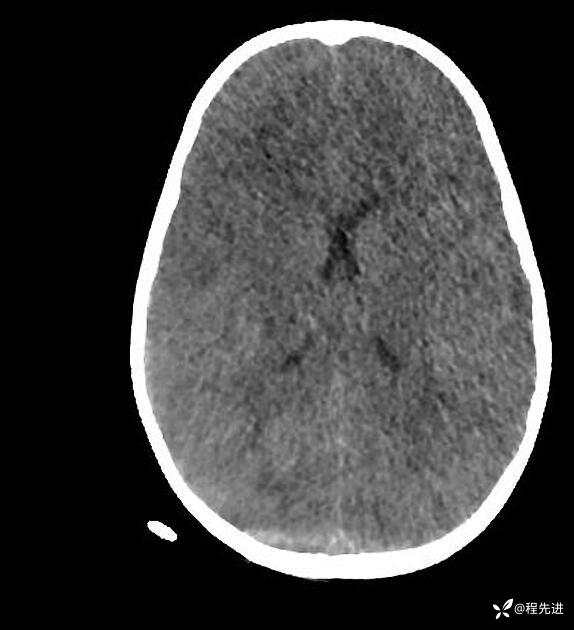

患者性别:男

患者年龄:5岁

简要病史:超速车祸外伤半小时

急诊CT平扫: